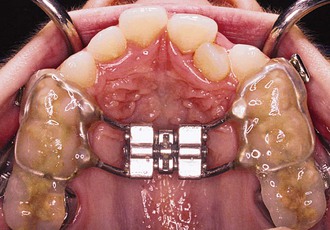

The protraction headgear force is applied via elastics to teeth or other devices supported by teeth and/or the palate. The primary aim is to transmit the force to the midface sutural interfaces. To achieve this, it is important to stabilize the maxilla as one unit (Fig. 16-1). In the primary dentition, it is advisable to use a cemented acrylic occlusal bite block or a removable acrylic plate with occlusal coverage (see Chapter 12). In patients with the mixed dentition and early permanent dentition, a removable acrylic plate (Fig. 16-2) should be used, supported by bands with headgear tubes on the molars or a rigid archwire with a palatal arch. Probably the best stabilization in patients with maxillary first molars is provided by a fixed rapid palatal expansion (RPE) device (Fig. 16-3). We prefer a Hyrax type of nonbonded device, as bonded RPEs (Fig. 16-4) interfere with the primary exfoliating teeth or teeth in the eruptive phase. Studies have also indicated that a simultaneous sutural expansion with an RPE at the start of protraction headgear treatment facilitates the anterior movement of the maxilla.19,20,26,27

Figure 16-1 A, Left and (B) right lateral views of an intraoral stabilization appliance. An acrylic bite block includes a heavy archwire to which a headgear tube is soldered. The bite block provides disocclusion to facilitate forward displacement of the maxilla and is cemented to posterior maxillary teeth.

Figure 16-2 Occlusal view of a removable intraoral stabilization appliance. The acrylic plate has a clasp that fits on a molar tube of a cemented band. This plate must be worn when the protraction appliance is in use.